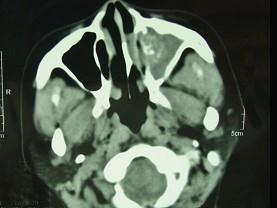

问题 男,41岁,左侧鼻腔胀痛半年余,CT检查如图,最可能诊断为 ( )

选项 A、真菌性鼻窦炎 B、上颌窦癌 C、化脓性鼻窦炎 D、变应性鼻窦炎 E、出血坏死性息肉

答案 A